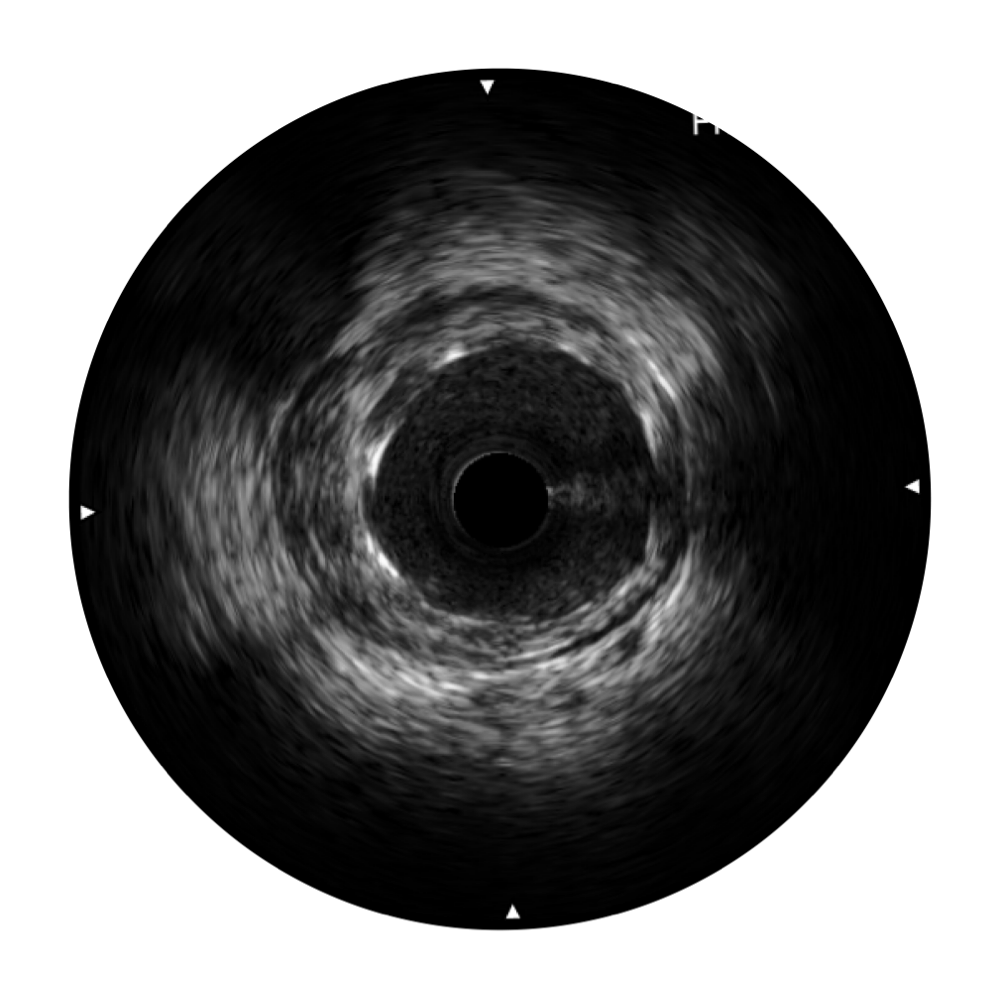

美狮贵宾会官网宽频IVUS图像

传统IVUS图像

对比传统IVUS导管成像,美狮贵宾会官网宽频IVUS图像的近场支架梁显影更细腻,远场中膜外血管仍清晰可辨,兼顾远中近,兼顾分辨力与穿透深度